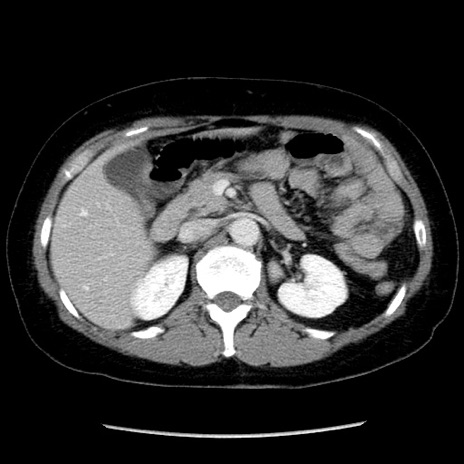

症例6(横断像)

【症例】50歳代女性

【主訴】下腹部痛

【現病歴】本日朝より下痢2回あり。 昼食を食べた後、嘔吐3回、下腹部痛認め、症状軽快せず、当院救急搬送。

【既往歴】卵巣癌術後(8年前に当院で卵巣摘出)

【身体所見】 意識清明、腹部:平坦、腸蠕動音→、やや硬、下腹部自発痛・圧痛あり、反跳痛あり、筋性防御なし。

【データ】WBC 16000、CRP 0.01